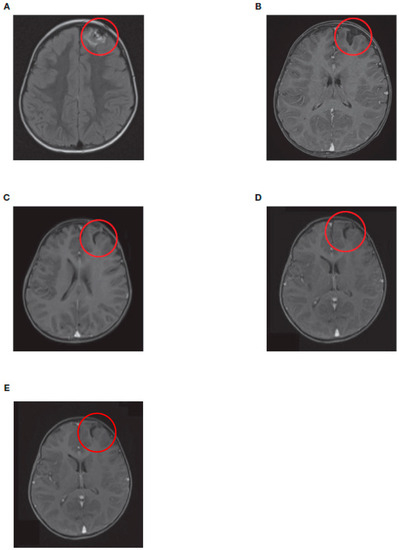

| 1 | 17 | Distant metastases (CNS only) Temporopolar dural metastasis (right cranial fossa) with local hemorrhage |

| 4 | 27 | Distant metastases (CNS only) Intracranial right frontal, left temporal, left frontobasal, involvement of the brain parenchyma, large liquid/hemorrhagic formations, |

| 13 | 14 | CNS only: parenchymatous cerebral relapse (frontal) |